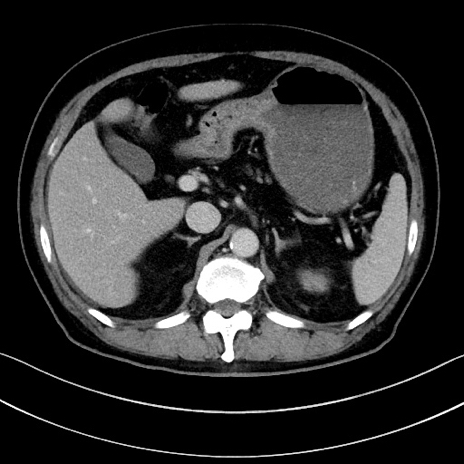

症例15(横断像)

【症例】70歳代男性

【主訴】腹痛

【現病歴】今朝から腹痛あり。全体的に痛い。特に左上の方。排ガスが今日はない。冷や汗が出る。

【既往歴】直腸癌術後

【身体所見】左側腹部〜上腹部に圧痛あり。腹膜刺激症状明らかなではない。軽度反跳痛。左下腹部に術後瘢痕あり。

【データ】WBC 7700、CRP 0.02